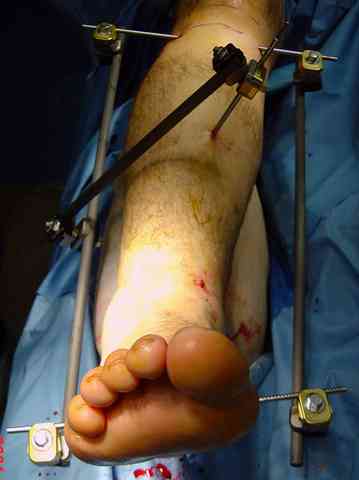

Яков изложил все необходимые аспекты лечения переломов пилона, и, не желая менять тему, решил выставить нашу точку зрения в двух клинических примерах.

При лечении внутрисуставных переломов типа "Pilon"

или "Tibial Plateau" на голени, применение простых

наружных фиксаторов типа "Spanning ExFix" или "Travelling ExFix" стал одним из стандартом этапного лечения.

В первые часы после поступления больным экстренно накладывается простой фиксатор из двух поперечно проведенных стержней или сооружается "Delta

Frame" в зависимости от места локализации, и проводится дистракция.

Здесь выставлена пара случаев перелома пилона, оба

случая леченные этапным наружным фиксатором.

Второй случай фиксирован аппаратом Илизарова.